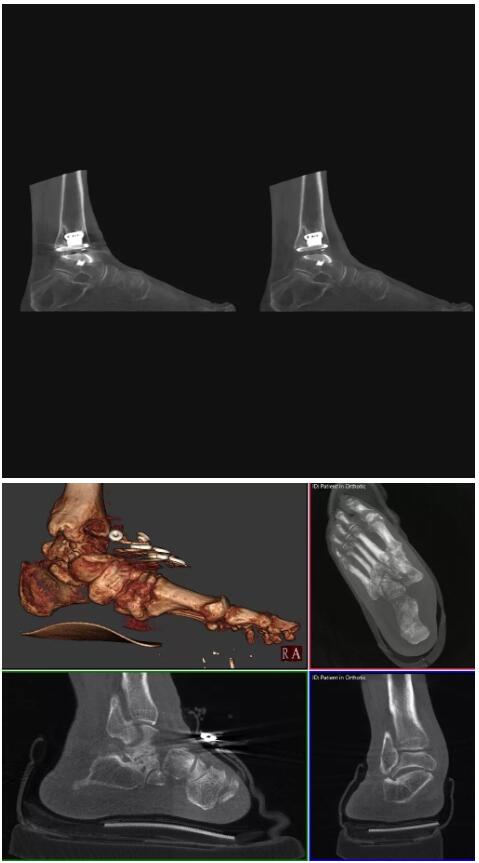

另外一款被稱(chēng)為世界上最小的CT,它的重量?jì)H300磅,不僅能夠掃查足部,還可以檢查膝蓋和上肢等。

與上面介紹的CT一樣,它同樣具有輻射低、占地空間?。?3*36)的特點(diǎn),隨開(kāi)隨用(支持直接接入墻上的插座)。

這款CT使用非常方便,通過(guò)上下移動(dòng)保持與患者的手臂或者雙腿齊平,掃描快速,僅需要30秒左右就可以完成掃查。

以上介紹的CT均來(lái)自國外同一家公司,這些CT均配置了可視化軟件,可以進(jìn)行切片、3D重建以及大型CT附帶的所有典型的操作功能。

以下是這些“特立獨行”的CT所拍出來(lái)的圖像: